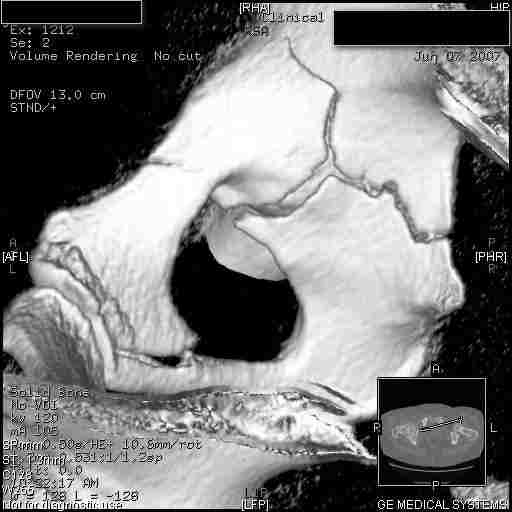

Следом 3d

|

Приветствую,Антон.Рункова рядом нет,но после полученных данных КТ,обсуждали совместно.Итог обсуждения-развернутый ответ дать не получится,т.к.срезы выбраны не информативные.Если ориентироваться на данные 3D,то ,ИМХО,можно лечить на вытяжении.

Спасибо, Салават и коллеги. Насколько я понял,нужны срезы в сагитальной и фронтальной плоскостях?